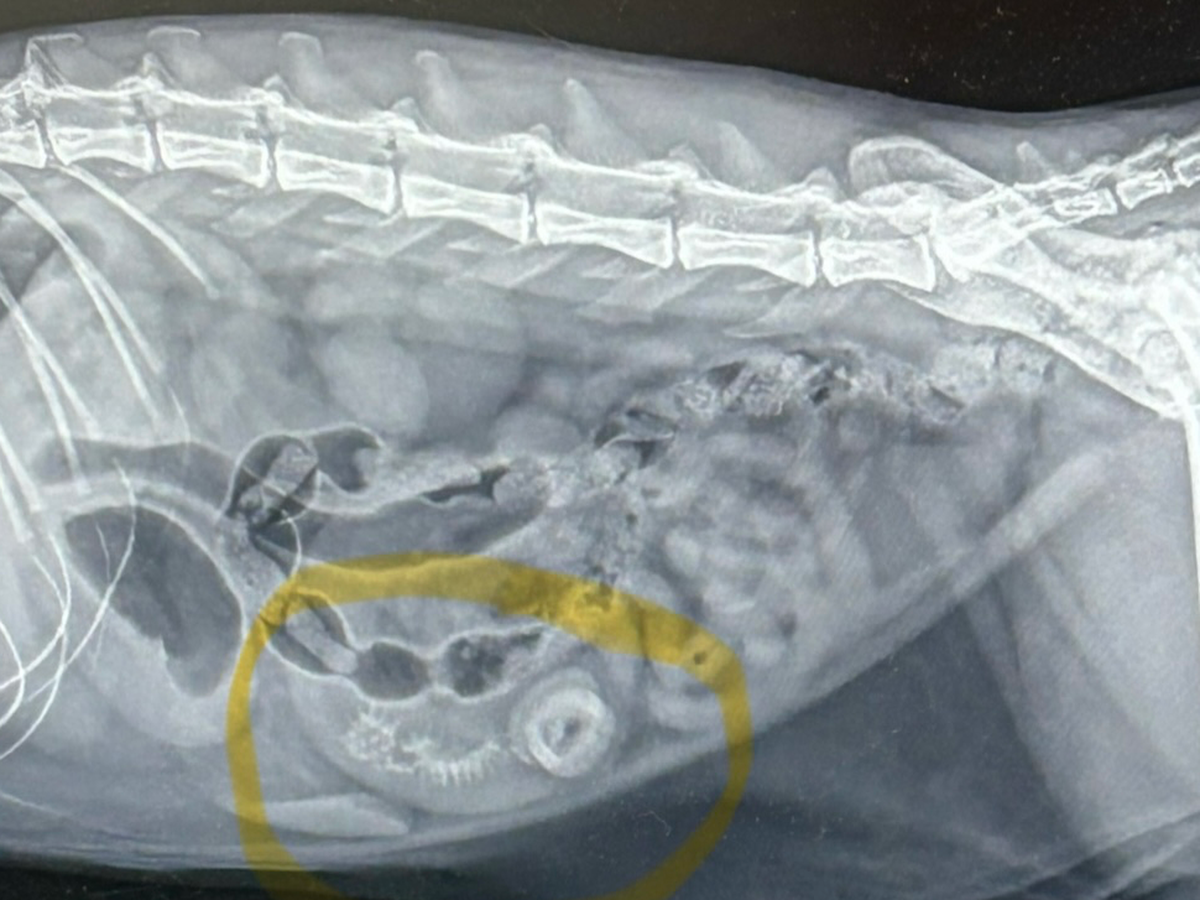

Hi, my name is Sarah and I have a 4-year-old spunky cat named Spence. Spence has recently gotten into things he shouldn’t and now needs to have surgery to remove objects in his intestines! This surgery is going to cost about $8,600 as he needs to be seen at VEG in Shrewsbury! No one likes to ask for help, but my spunky boy still has so much life to live! Any and all monetary help, likes, shares, and word of mouth helps! Donations go toward payment of surgery. Thank you for taking the time to read and care about Spence!